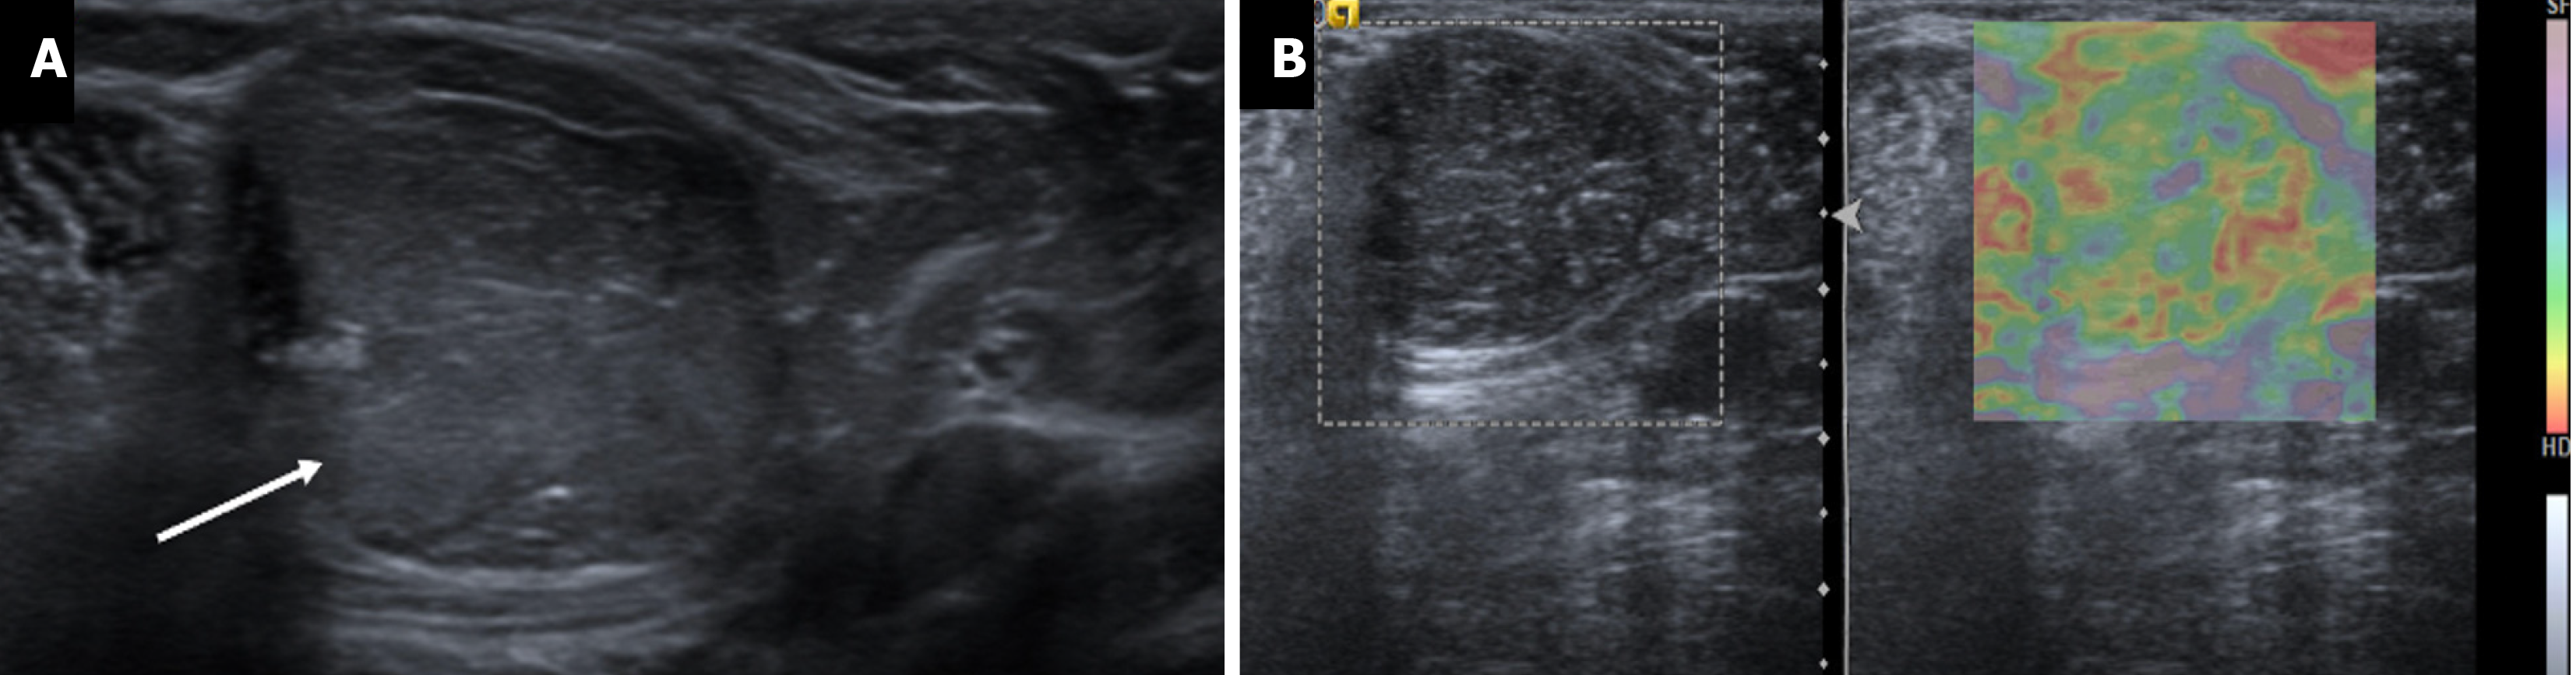

Figure 13  Lipoma in a 34-year-old male with a palpable mass in the axilla.

A: Ultrasound; B: Elastography images showing a circumscribed oval homo